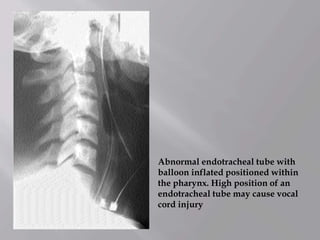

Abnormal endotracheal tube with

balloon inflated positioned within

the pharynx. High position of an

endotracheal tube may cause vocal

cord injury